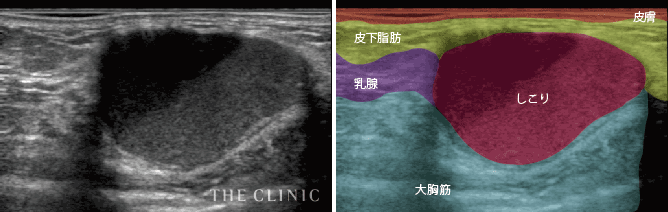

- 脂肪注入によるしこりのほとんどが、中に壊死して液体となった脂肪が入っています。その部分がエコーでは黒く映し出されます。

しこりの治療は、まず検査で良性か悪性か、他にもサイズや石灰化を起こしていないかなどを判断します。脂肪注入でできたしこりの場合、小さいものなら時間とともに吸収されるので、そのままでも問題ありません。ただ、大き過ぎるものや炎症を起こしているものなどは処置が必要となります。

基本的には、脂肪溶解注射でしこり内の脂肪を溶かしたり、脂肪吸引で除去したりすることで除去できます。ただし、治療中もエコー画像などをリアルタイムで確認し、取り残しを防ぐことが重要です。